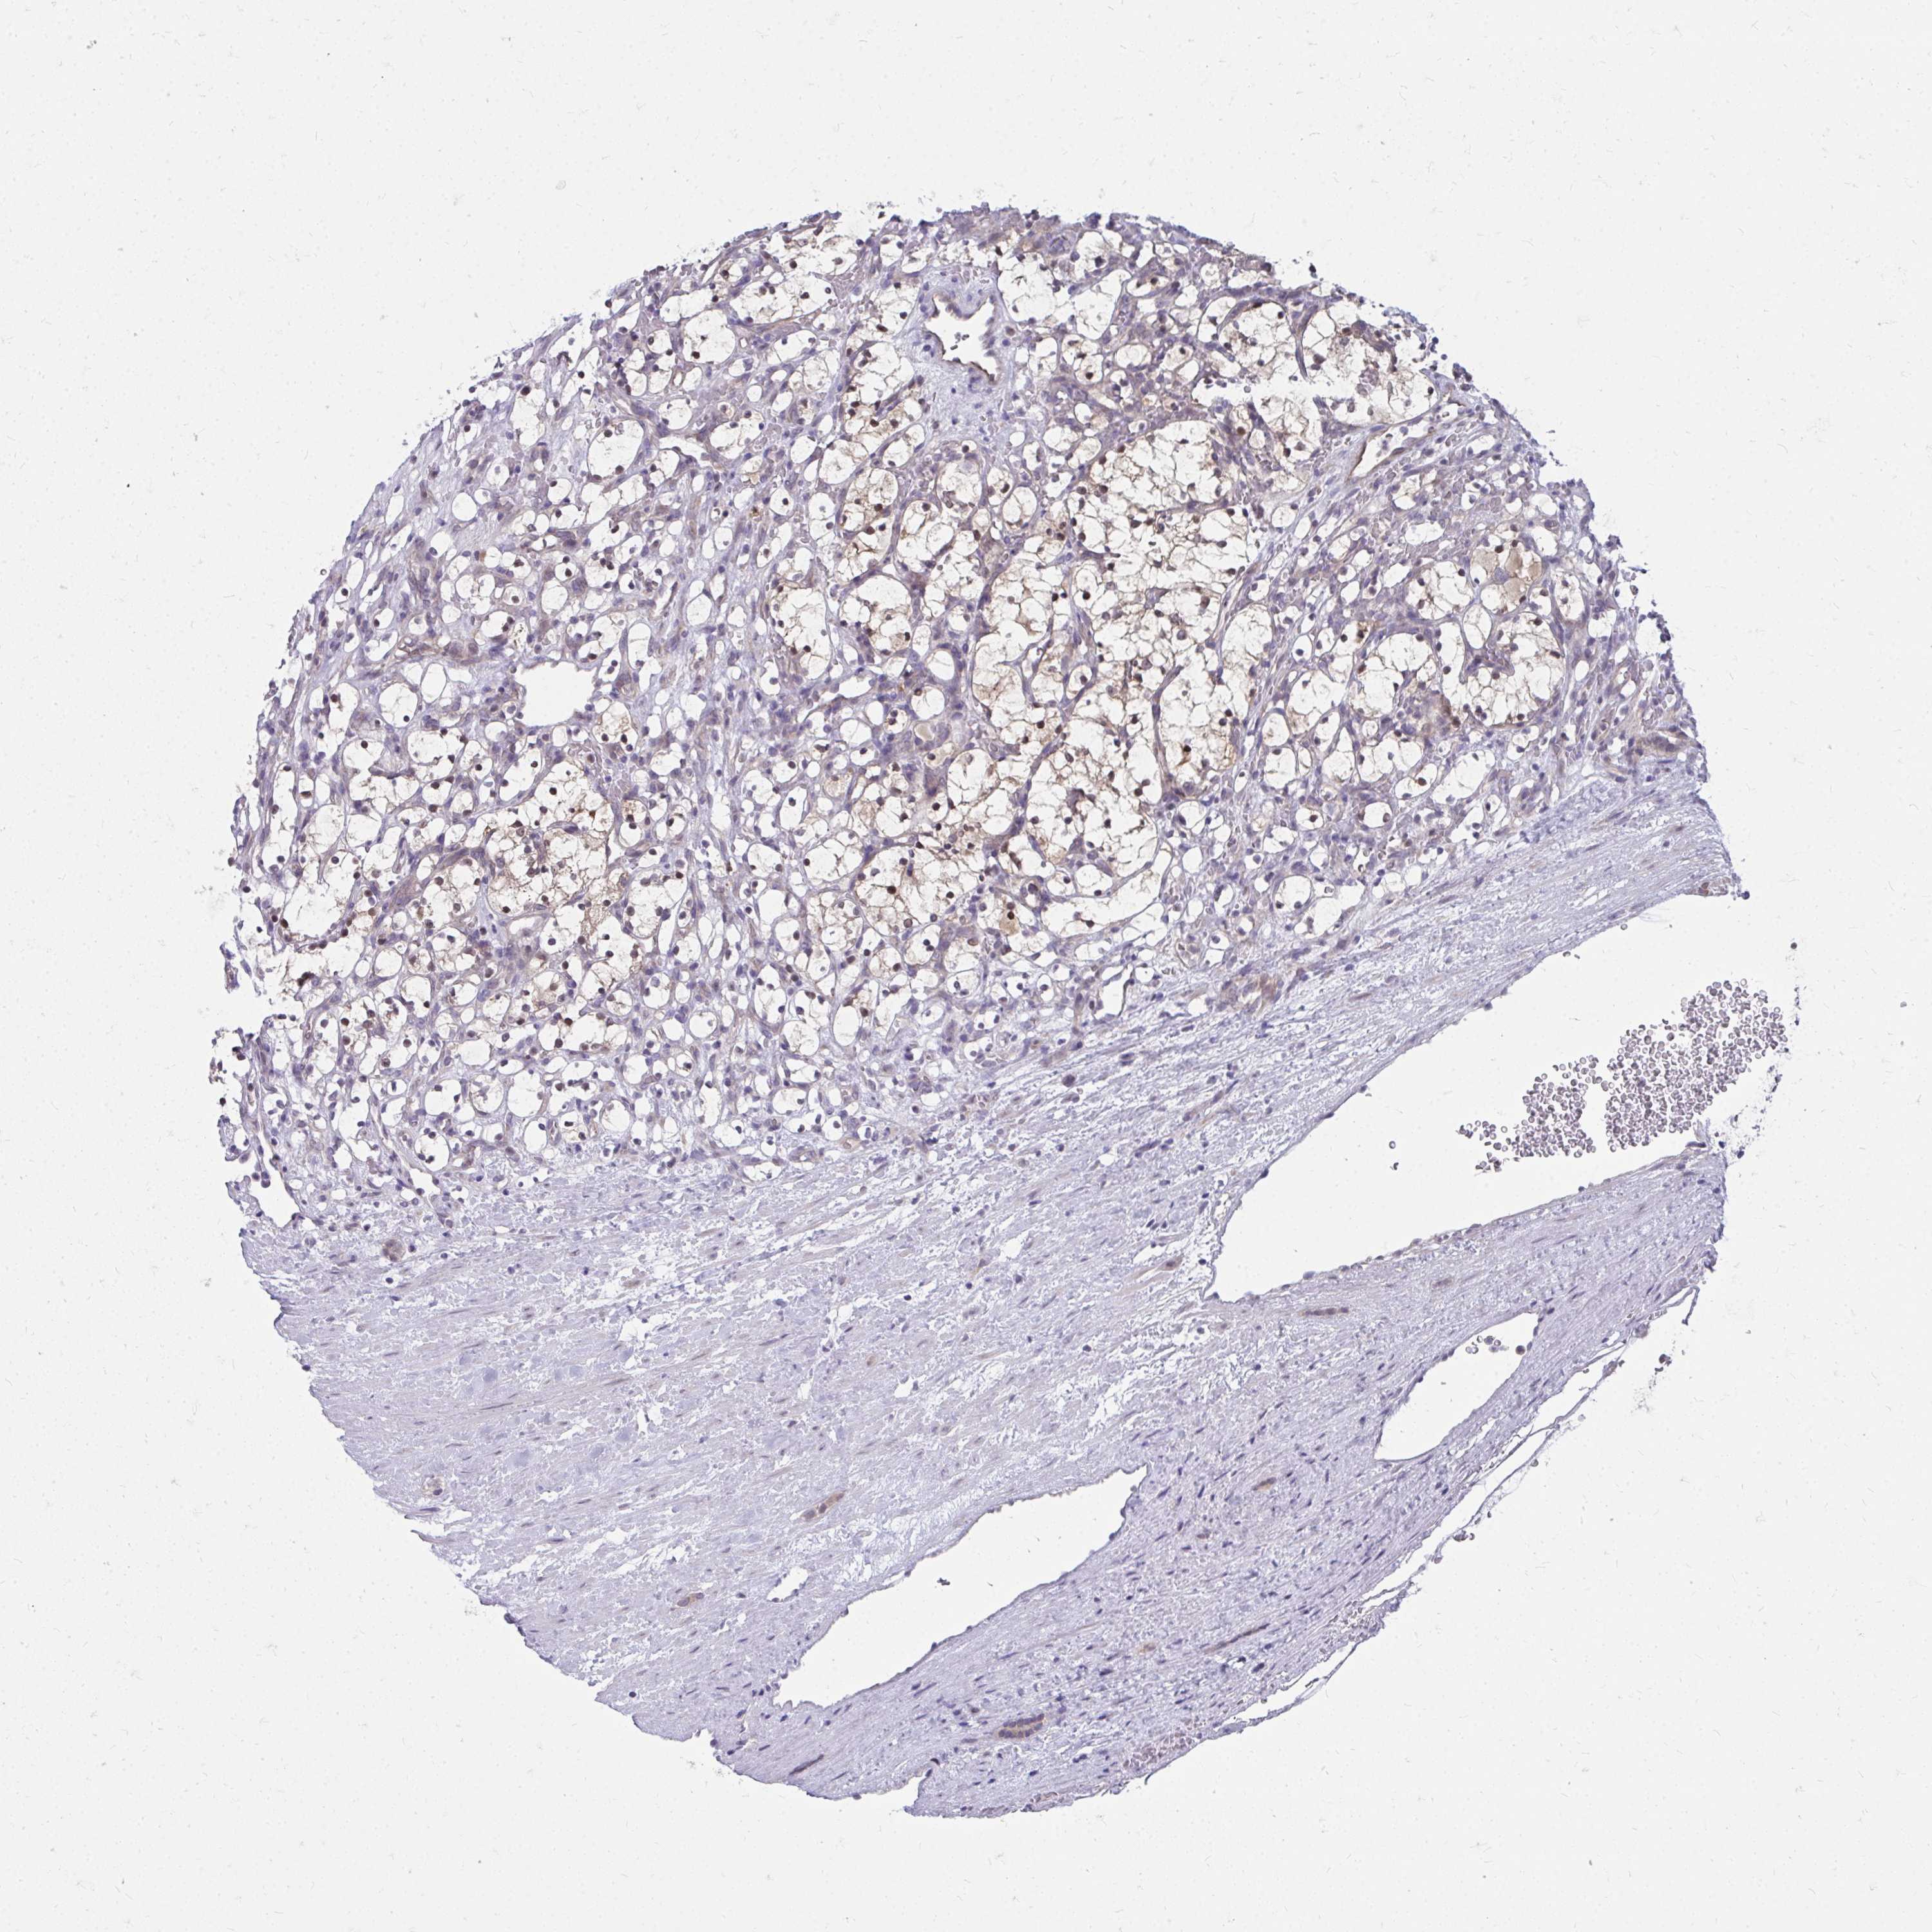

KIDNEY RENAL CLEAR CELL CARCINOMA (VALIDATION) - Interactive survival scatter ploti

The Survival Scatter plot shows the clinical status (i.e. dead or alive) for all individuals in the patient cohort, based on the same data that underlies the corresponding Kaplan-Meier plots. Patients that are alive at last time for follow-up are shown in blue and patients who have died during the study are shown in red.

The x-axis shows the expression levels (FPKM) of the investigated gene in the tumor tissue at the time of diagnosis. The y-axis shows the follow-up time after diagnosis (years). Both axes are complimented with kernel density curves demonstrating the data density over the axes. The top density plot shows the expression levels (FPKM) distribution among dead (red) and alive patients (blue). The right density plot shows the data density of the survived years of dead patients with high and low expression levels respectively, stratified using the cutoff indicated by the vertical dashed line through the Survival Scatter plot. This cutoff is automatically defined based on the FPKM cutoff that minimizes the p-score. The cutoff can be changed by dragging the vertical line or by entering a cutoff value in the square labeled "Current cut-off".

Under the Survival Scatter plot the p-score landscape (black curve; left axis) is shown together with dead median separation (red curve; right axis). Dead median separation is the difference in median mRNA expression between patients who have died with high and low expression, respectively. It is calculated as follows: median FPKM expression of dead patients with high expression - median FPKM expression of dead patients with low expression. This is intended to aid the user in visually exploring custom cutoffs and the associated p-scores and dead median separation.

Individual patient data is displayed and can be filtered by clicking on one or more of the category buttons on the top of the page. Categories describing expression level and patient information include: high, low, alive, dead, female, male and tumor stages. The scale of the x-axis can be toggled between linear and log-scale by clicking on the "x log" button. Mouse-over function shows TCGA ID, patient information and mRNA expression (FPKM) for each patient.

& Survival analysisi

Kaplan-Meier plots summarize results from analysis of correlation between mRNA expression level and patient survival. Patients were divided based on level of expression into one of the two groups "low" (under cut off) or "high" (over cut off). X-axis shows time for survival (years) and y-axis shows the probability of survival, where 1.0 corresponds to 100 percent.

MROH8 is not prognostic in Kidney Renal Clear Cell Carcinoma (validation)

TCGA RNA samplesi

RNA-seq data is reported as average FPKM (number Fragments Per Kilobase of exon per Million reads), generated by the The Cancer Genome Atlas (TCGA) .

Normal distribution across the dataset is visualized with box plots, shown as median and 25th and 75th percentiles. Points are displayed as outliers if they are above or below 1.5 times the interquartile range. FPKM values of the individual samples are presented next to the box plot.

Average pTPM 0.8

Number of samples 100